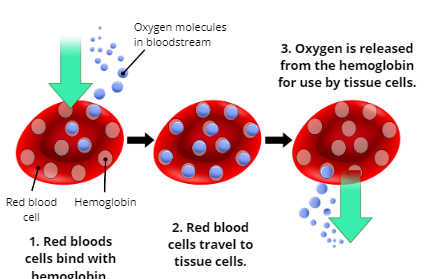

Oxygenation

the process of supplying oxygen to the body’s tissue cells

Explain the Process of Oxygenation

1. Oxygen molecules in the bloodstream enter red blood cells and bind with hemoglobin

2. Red blood cells travel to tissue cells

3. Oxygen is released from the hemoglobin for use by tissue cells